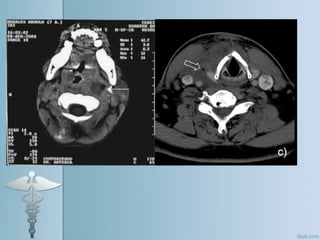

Complicaciones supurativas

• Absceso parafaríngeo

 Se extiende lateralmente a los músculos constrictores

faríngeos en el espacio parafaríngeo.

 Disfagia y odinofagia , dolor laterocervical y tortícolis.

 Abombamiento de la pared lateral de la faringe por

detrás de la amígdala y que desciende hasta la

hipofaringe.

 Realizar una TAC cervical

 Tratamiento: antibióticos y corticoides intravenosos;

drenaje vía externa por cervicotomía.

 Riesgo de Tromboflebitis séptica de Vena yugular interna

(enfermedad de Lemierre), con riesgo elevado de TEP

séptico.